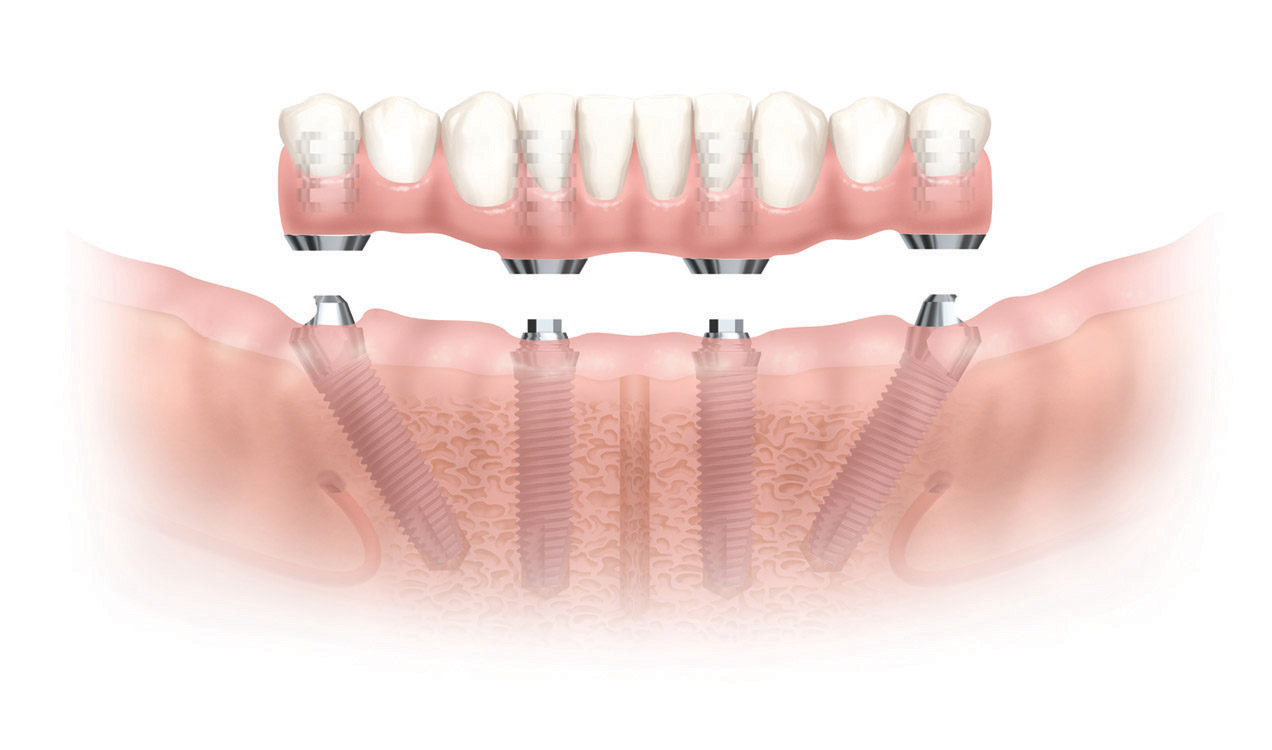

Il dott. Malò propone, con la sua tecnica, l’utilizzo di soli quattro impianti (da ciò il famoso nome “all on 4”) che per la loro lunghezza ed inclinazione nell’osso assicurano in tempo immediato la possibilità di sostenere arcate di denti parziali o totali.

Nel nostro Centro di Implantologia Dentale abbiamo importato questa tecnica, ormai così consolidata che riporta consensi positivi a livello mondiale, personalizzandola con l’aggiunta di due impianti nell’arcata superiore (realizzando una arcata dentaria di 12 denti sostenuta da 6 impianti)

e un impianto nell’arcata inferiore (realizzando una arcata dentaria di 12 denti sostenuta da 5 impianti).

Nel nostro Centro abbiamo scelto di utilizzare un numero superiore di impianti rispetto alla tecnica di Malò in modo da assicurare nel tempo una maggiore affidabilità e durata degli impianti così sottoposti ad un carico masticatorio di 12 denti (come nostro protocollo testato). La personalizzazione della tecnica è stata eseguita a diversi livelli, che vanno dalla progettazione tecnologica dell’intervento, al controllo totale della sintomatologia intra e post operatoria, alla guida alimentare post chirurgica e alla educazione del paziente alle nuove tecniche di igiene orale.